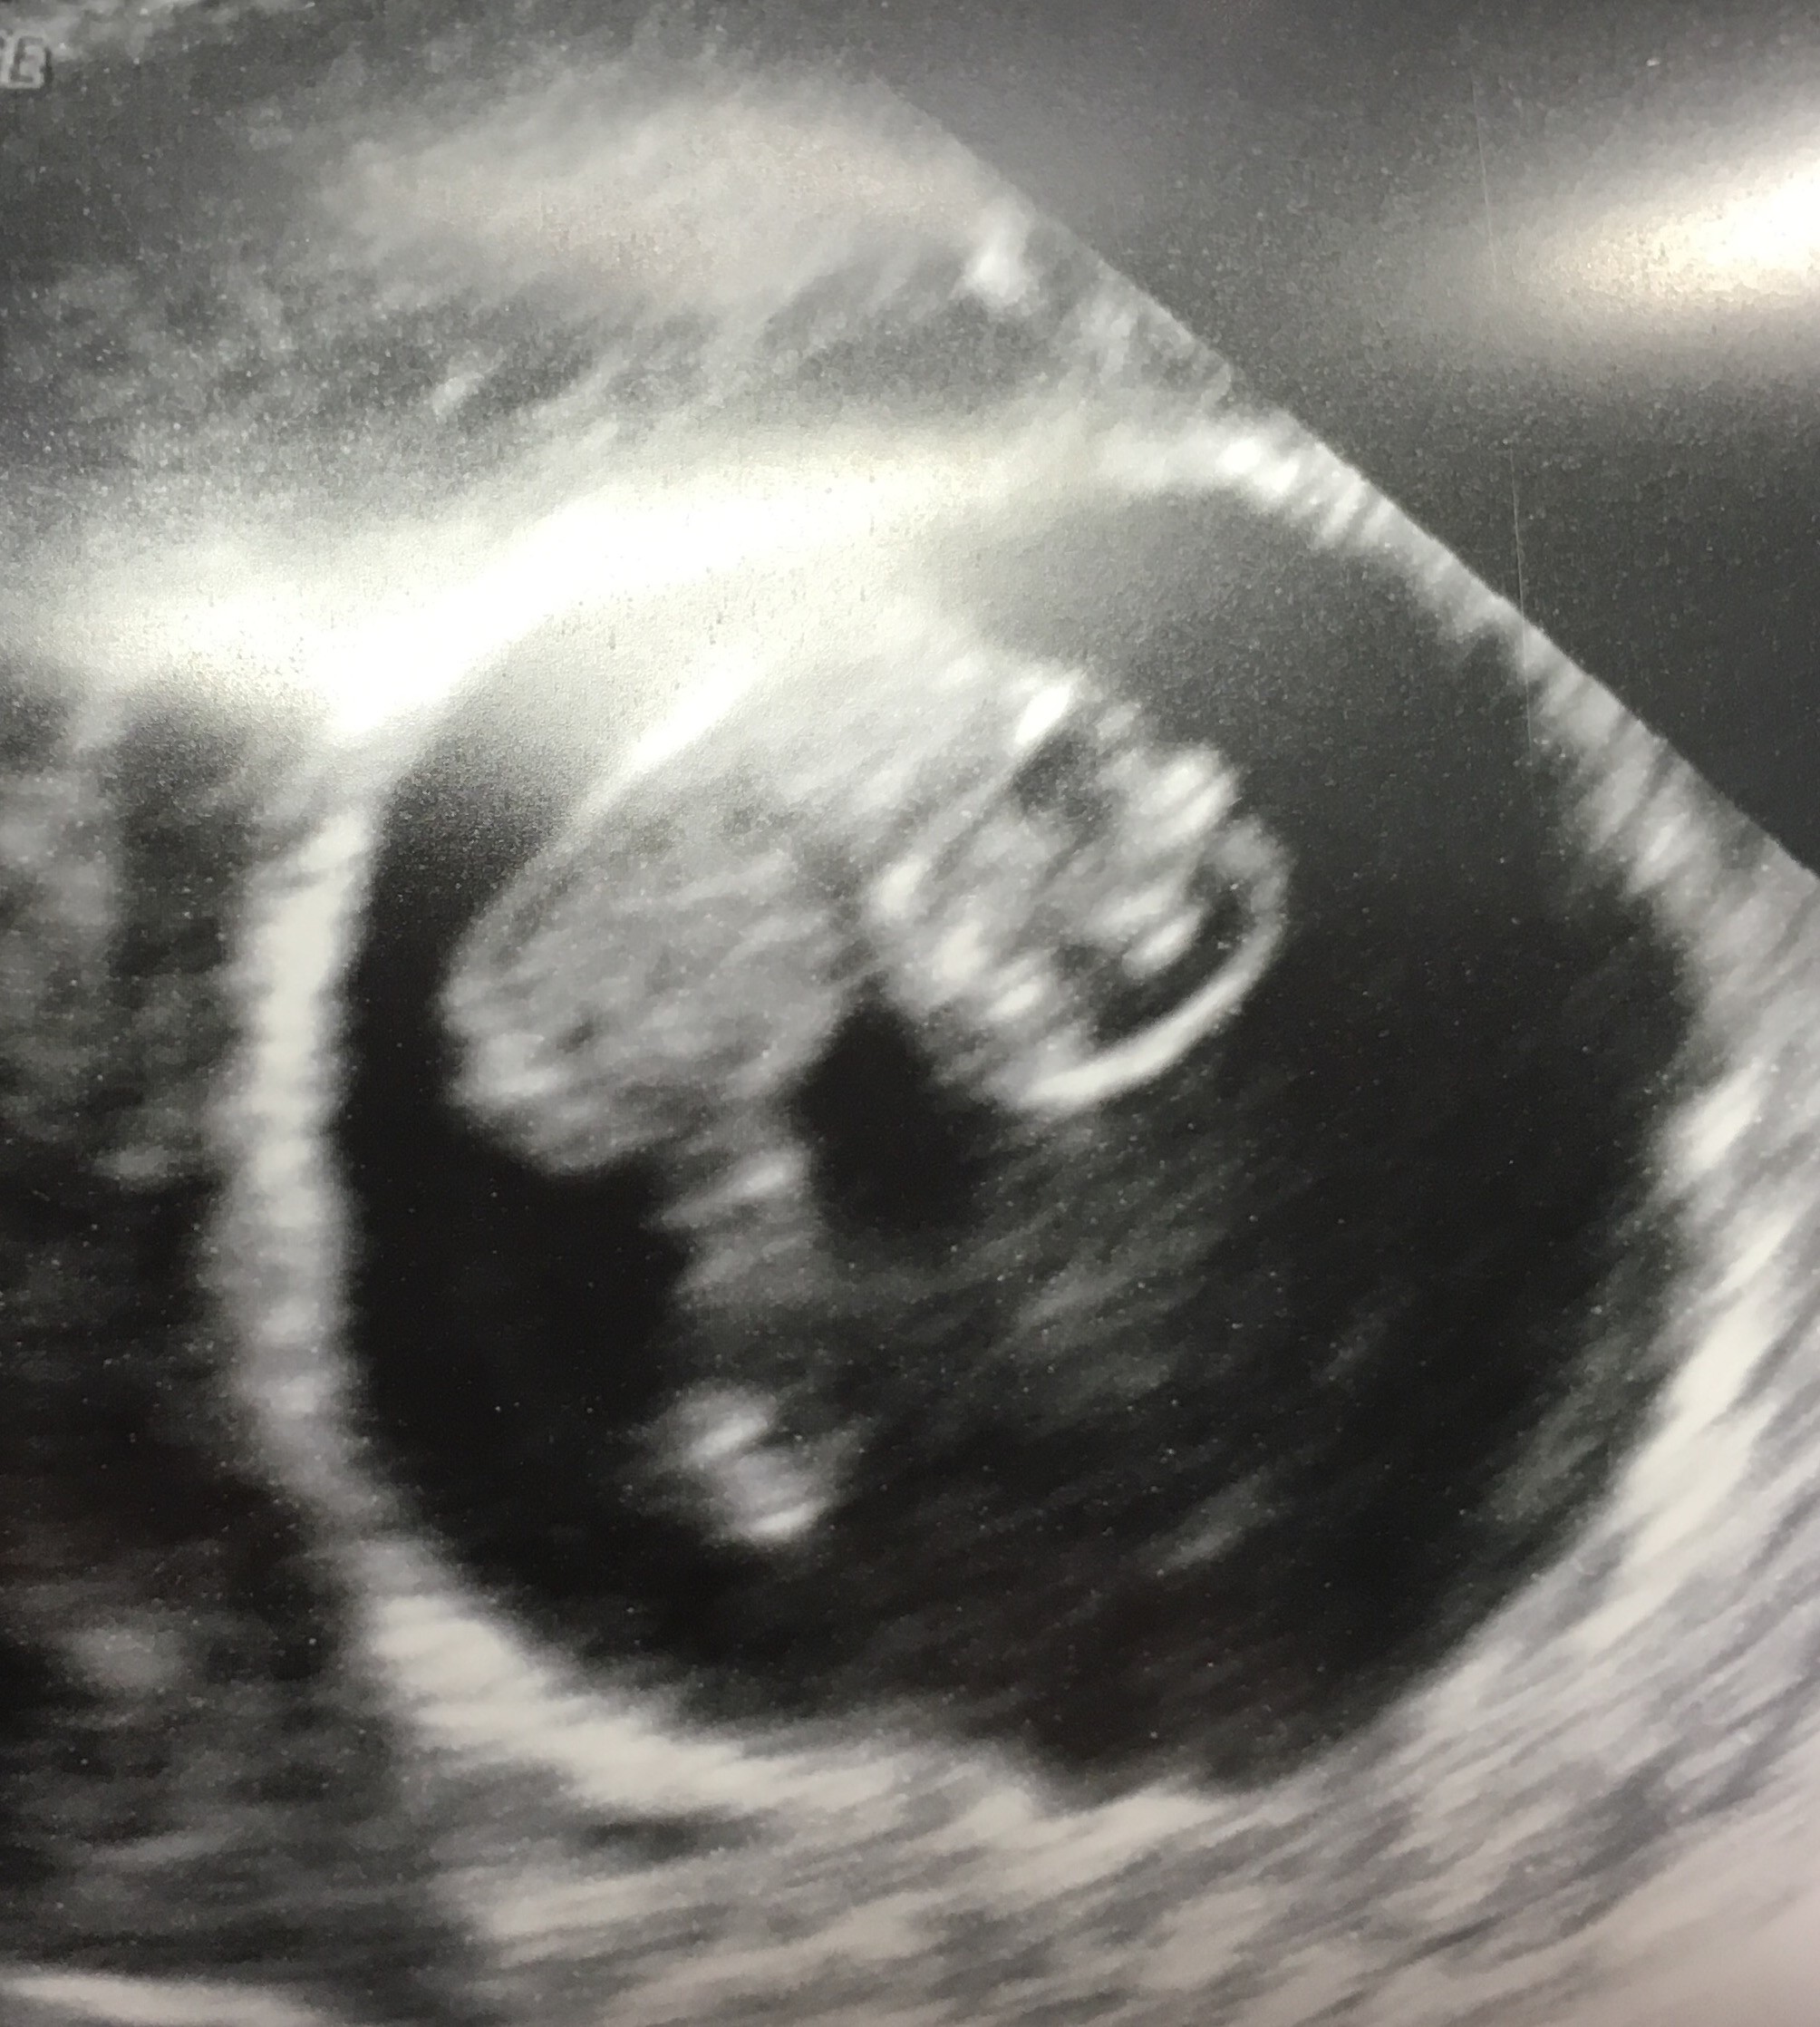

Tak I teraz Bardzo sie martwie o drugie nie wiem jak dalej to zniose co myslecEwa trudna sytuacja ale mimo to gratuluję jednego serduszka, wiem że już pokochalaś oba tak jak ja swoje

Ewciu kochana myśl pozytywnie!!!! Tak musiało być. Ten jeden jest małym twardzielem i na pewno zostanie z tobą. Zobaczysz. Tylko nie załamuj się i bądź nastawiona pozytywnie. Odpocznij,prześpij się kochana i wierz!!!!Tak I teraz Bardzo sie martwie o drugie nie wiem jak dalej to zniose co myslec![]()